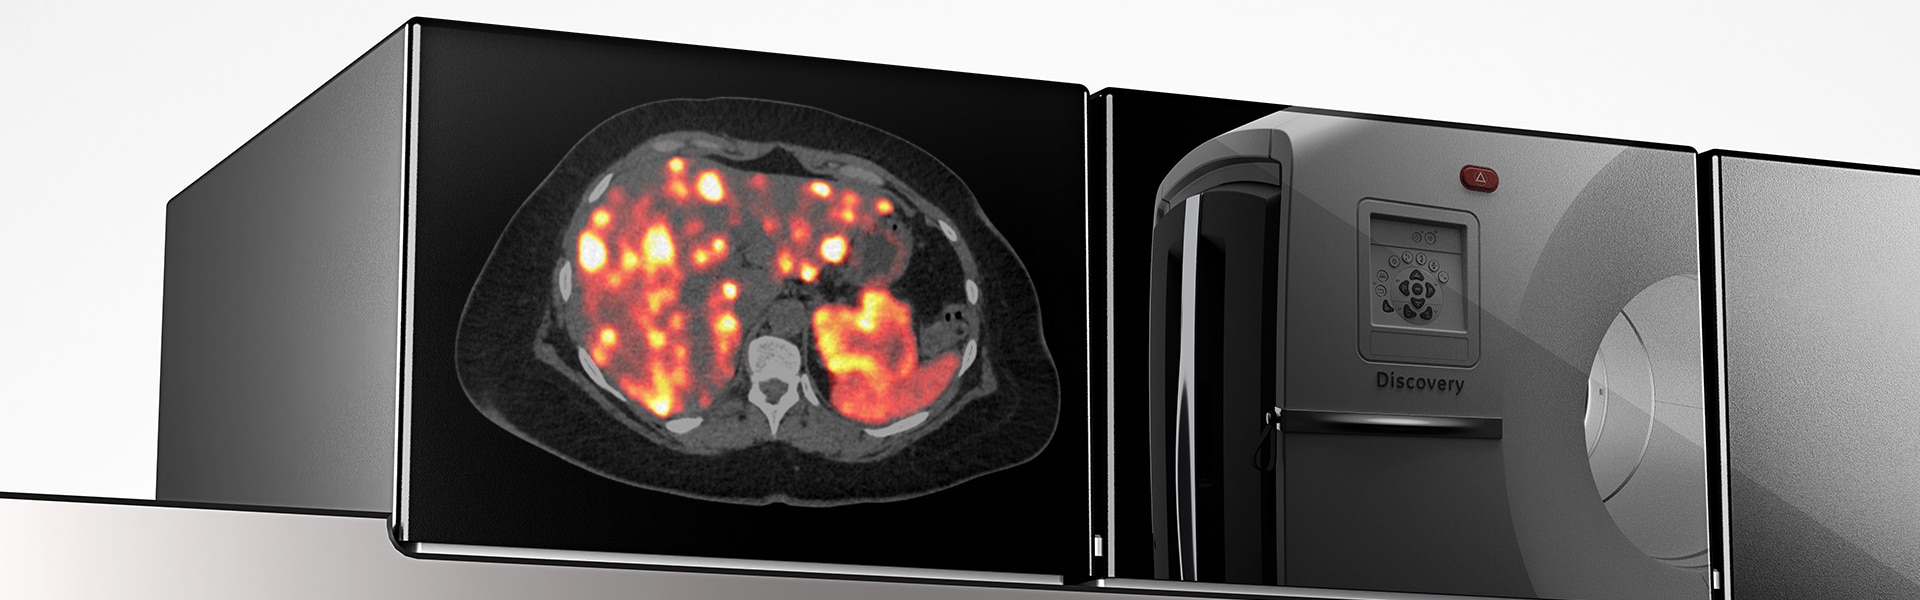

SUV accuracy

Up to two times improvement in PET quantitation accuracy (SUVmean) with Q.Clear

Accurate data points to trusted treatment

- Up to a 2x improvement in image quality (SNR)

- Up to a 2x improvement in quantitative SUV (SUVmean)